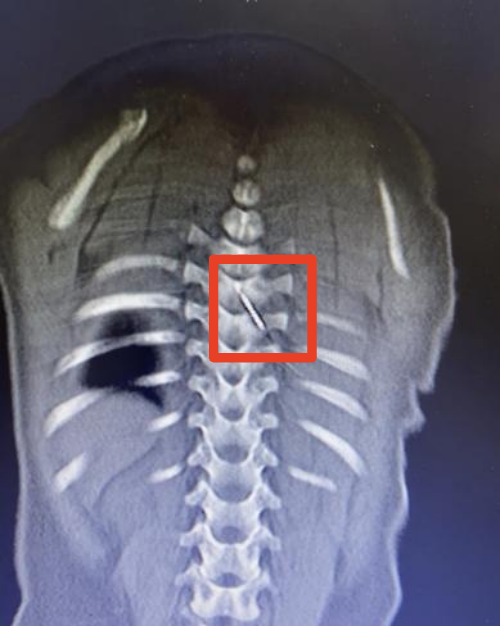

12月5日深夜,仅9个月大的男婴琪琪(化名)被紧急送往国家儿童区域医疗中心、安徽省儿童医院救治。原来,一根长约3厘米的缝衣针裹在被子里,竟在孩子睡觉时悄悄“钻”进了他的后背,并随着身体移动不断深入,最终扎入了琪琪的脊柱内,紧贴脊髓的危险区域。

凌晨2点,手术室亮起了无影灯。该院儿童骨科、麻醉与围术期医学科、儿童重症医学科、影像科多学科专家组成的抢救团队严阵以待。通过三维CT影像,医生们精确还原了针的走行路径和周围解剖结构。

当手术刀切开琪琪背部皮肤时,所有人都屏住了呼吸。在高倍显微镜下,在幼儿细小的脊柱解剖结构间小心分离,避开重要血管与神经,最终于脊髓腔外侧安全区域,精准、完整地取出缝衣针。